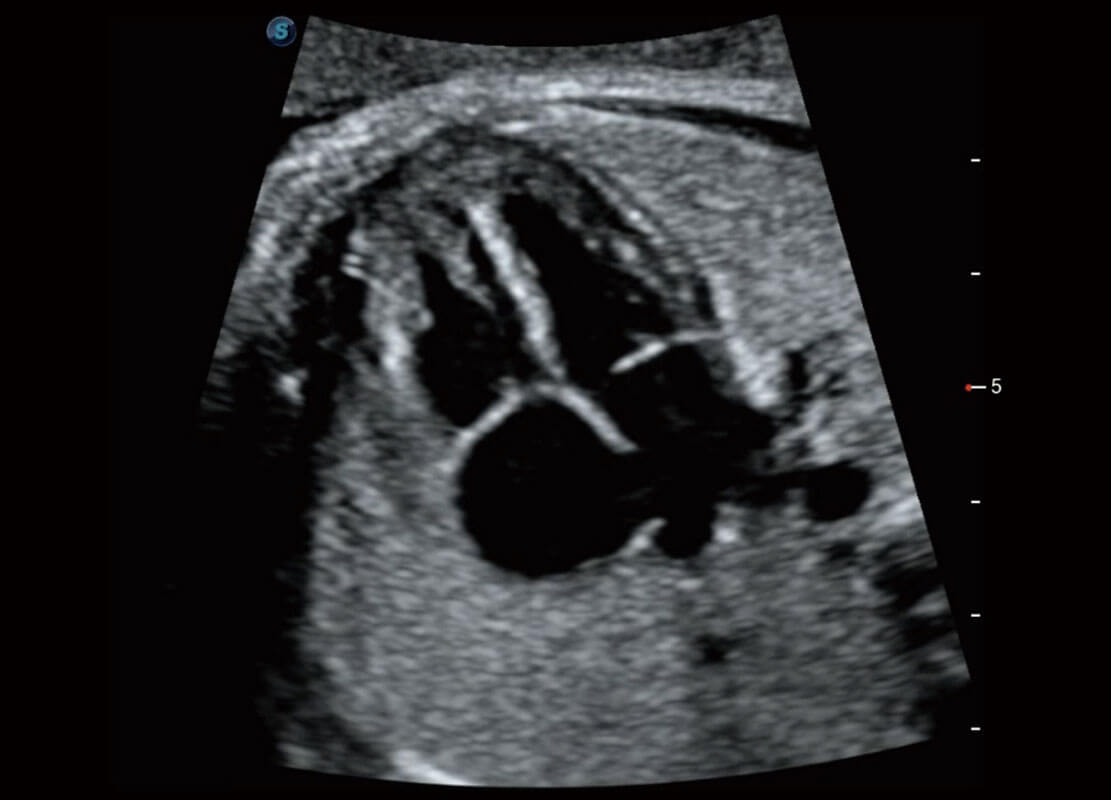

P60搭载一系列胎儿心脏成像技术,实现精细的胎儿心脏评估。

四腔切面

右室双出口

胎心容积成像